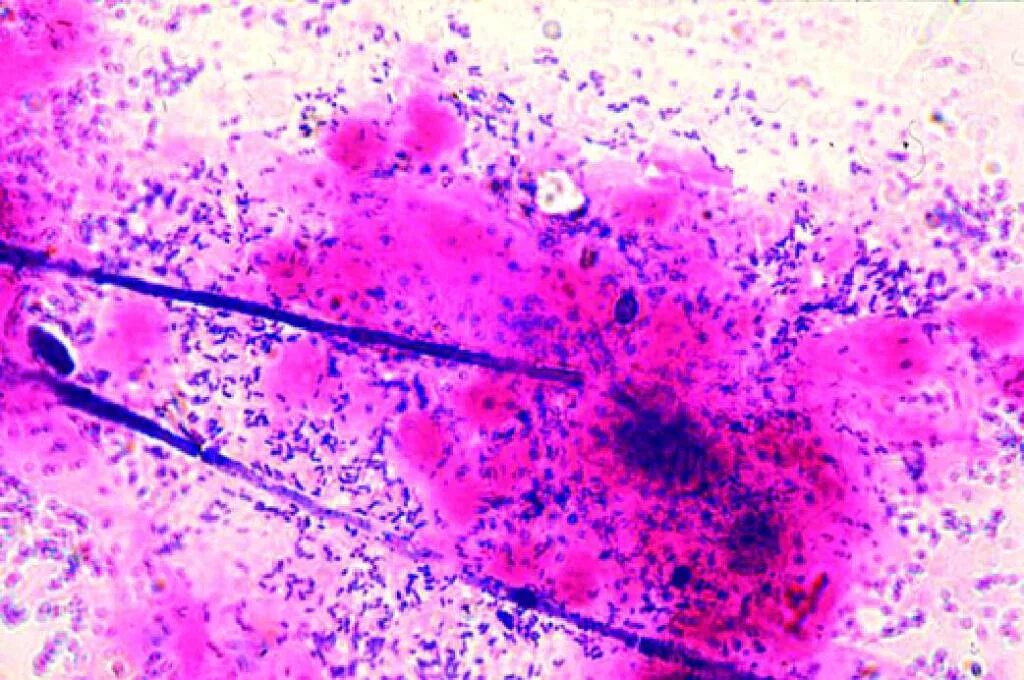

Бациллярная микрофлора